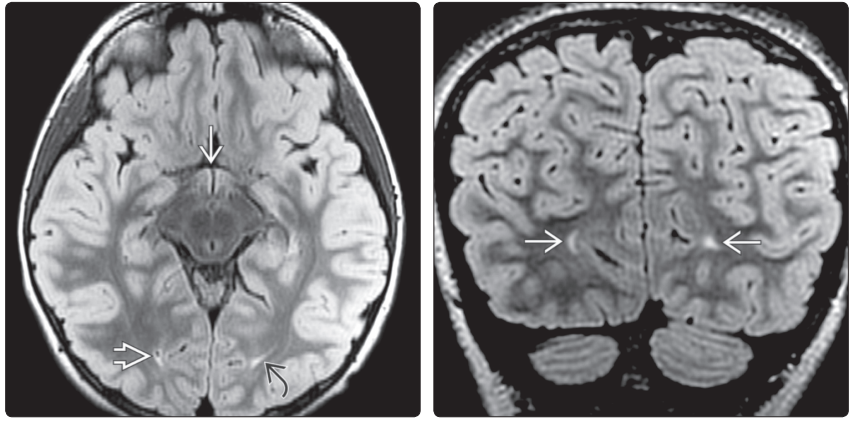

(左图)MR横断位T1WI示:中脑导水管狭窄引起侧脑室颞角→和第三脑室前隐窝↪显著扩张。(右图)MR冠状位T2WI示:包括颞角(左侧显示较好 ⇒,杏仁核下方扩张)在内侧脑室明显扩张。第三脑室↪前隐窝下缘膨胀、壁变薄